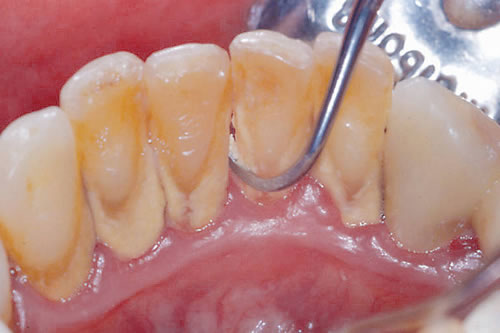

歯垢(プラーク)

歯に付着している細菌とその細菌が作り出すもの

歯石

歯垢(プラーク)が石灰化して固まったもの

ステイン(着色)

たばこのヤニやコーヒー、紅茶、赤ワインなどの色素が沈着したものなどがあります。

虫歯・歯周病の原因となるこれらの汚れをキレイにするのが歯のクリーニングです。

口腔内の衛生管理のプロフェッショナルである歯科衛生士が「歯の表面」「歯と歯のすき間」「歯周ポケットの内部」に付着したプラークや歯石を専用器具で徹底的に除去します。

スケーラーで歯茎の際まで歯石除去をおこなうとどうしても歯茎に触れて軽い痛みを感じることがあります。

また歯石のついている歯茎は弱っているためちょっとした刺激で出血することもよくあります。

それらは一時的なものですのでクリーニングにおいては通常治療後すぐに治まります。

これは歯ぐきにもともと炎症のある方に起きやすく、歯茎が健康な方はPMTCをしても出血は見られません。